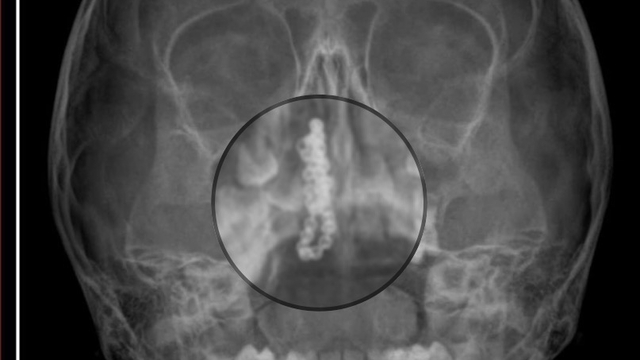

Kentte yaşayan Gökhan-Nalan Tekin çifti, yaklaşık 4 ay önce şiddetli burun kanamasının yanı sıra akıntı şikayetleriyle kızları Polen'i, bir özel hastaneye götürdü. Burada röntgeni çekilip, tetkikleri tamamlanan küçük kıza, iddiaya göre enfeksiyon teşhisi konulup, ilaç verildi. Eve dönen aile, kanama ve akıntının geçmemesi üzerine bu kez Rize Devlet Hastanesi'ne giderek Kulak Burun Boğaz Polikliniği'ne başvurdu. Devlet hastanesindeki doktorun incelemesi ve kapsamlı röntgen çekilmesi sonrası Polen'in burnunda metal cisim olduğu fark edildi. 2 yıldır burunda kaldığı değerlendirilip, küçük top şeklinde tırnak makası zinciri olduğu belirlenen cisim, başarılı ameliyatla çıkarıldı. Bir süre tedavisi sürdürülen Polen, sağlığına kavuşunca taburcu edildi. Özel hastane yetkilileri, konuyla ilgili açıklama yapmazken; aile suç duyurusunda bulunacaklarını söyledi.

Kızının burnundan sürekli siyah renkte akıntı olduğunu anlatan Gökhan Tekin, "Çocuğumun burnundan kanama ile sürekli siyah akıntı geliyordu. Özel hastaneye götürdüm. Özel hastanede film çekildi, hiçbir bulguya rastlanılmadığı söylendi. O siyah leke de enfeksiyona dayalı olan bir şey olduğu bize söylendi. Eve geldik, akıntı sürmesi üzerine bu kez devlet hastanesine başvurduk. Burunda metal zinciri fark ettiler. Böyle bir ihmalkarlık olabilir mi? Özel hastaneye gidiyoruz, paramızla rezil oluyoruz. Zincir, 2 yıldır burnunda ve devletimizin hastanesinde iyi bir doktorumuz zinciri ortaya çıkarıyor, kızım ölümden dönüyor. Ben sonuna kadar bu işin peşini bırakmayacağım. Sonuna kadar hukuk mücadelesi vereceğim. Bu da diğer hastalarımıza ibret olsun. İşte, bakın koca bir zincir. 'Bulguya rastlanılmadı' deniliyor" dedi.

Kızının ameliyat sonrası durumunun iyi olduğunu söyleyen Tekin, "İnanır mısınız bize 'Evde soba mı yanıyor? Acaba kömür isten dolayı mıdır bu?' dendi. Böyle bir şey olabilir mi? Ameliyattan çıkan parmağım kadar zincir. Devlet hastanesindeki doktor da 'Bu nasıl gözden kaçılabilir? Böyle bir pozisyon nasıl görülmeyebilir?' yorumunda bulundu. Allah'a şükür olsun atlattık. Şu anda durumu, vaziyeti iyidir. Ben şuna inanıyorum doktor da bir şans işidir. Bakın paramızla özele gideriz ya hani bizde, daha iyi ilgilenirler. Oysa devlet hastanesindeki doktorumuz olayı meydana çıkardı" diye konuştu.